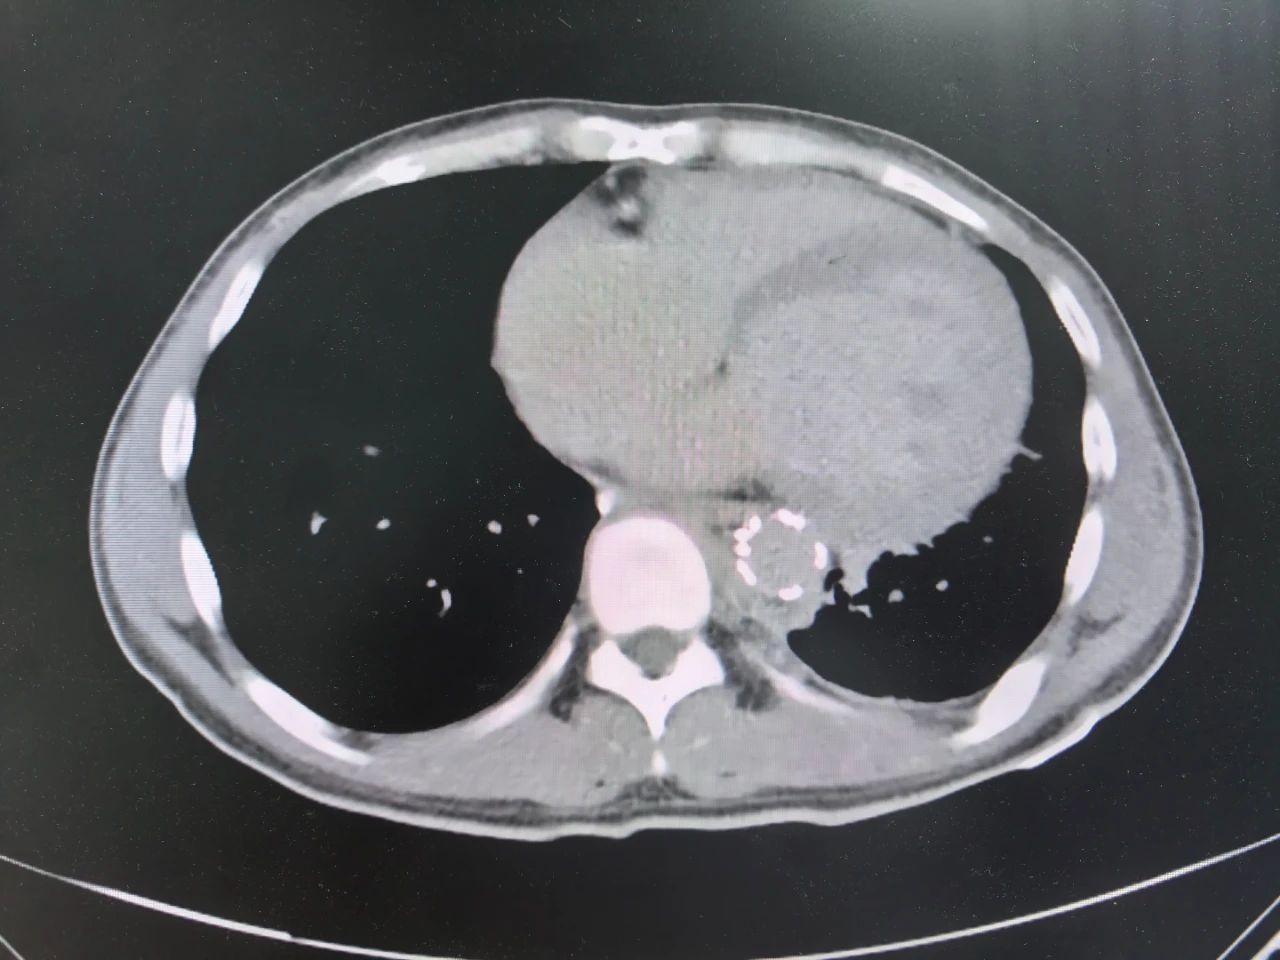

从血管破裂到康复出院仅用5天创造生机

令人振奋的是,从主动脉破裂出血的危急状态到症状完全缓解、血管修复,仅用5天患者便康复出院。整个救治过程中,在多学科团队通力配合下,经过及时有效的诊疗,患者病情得到妥善处理。

术后复查血性胸腔积液消失